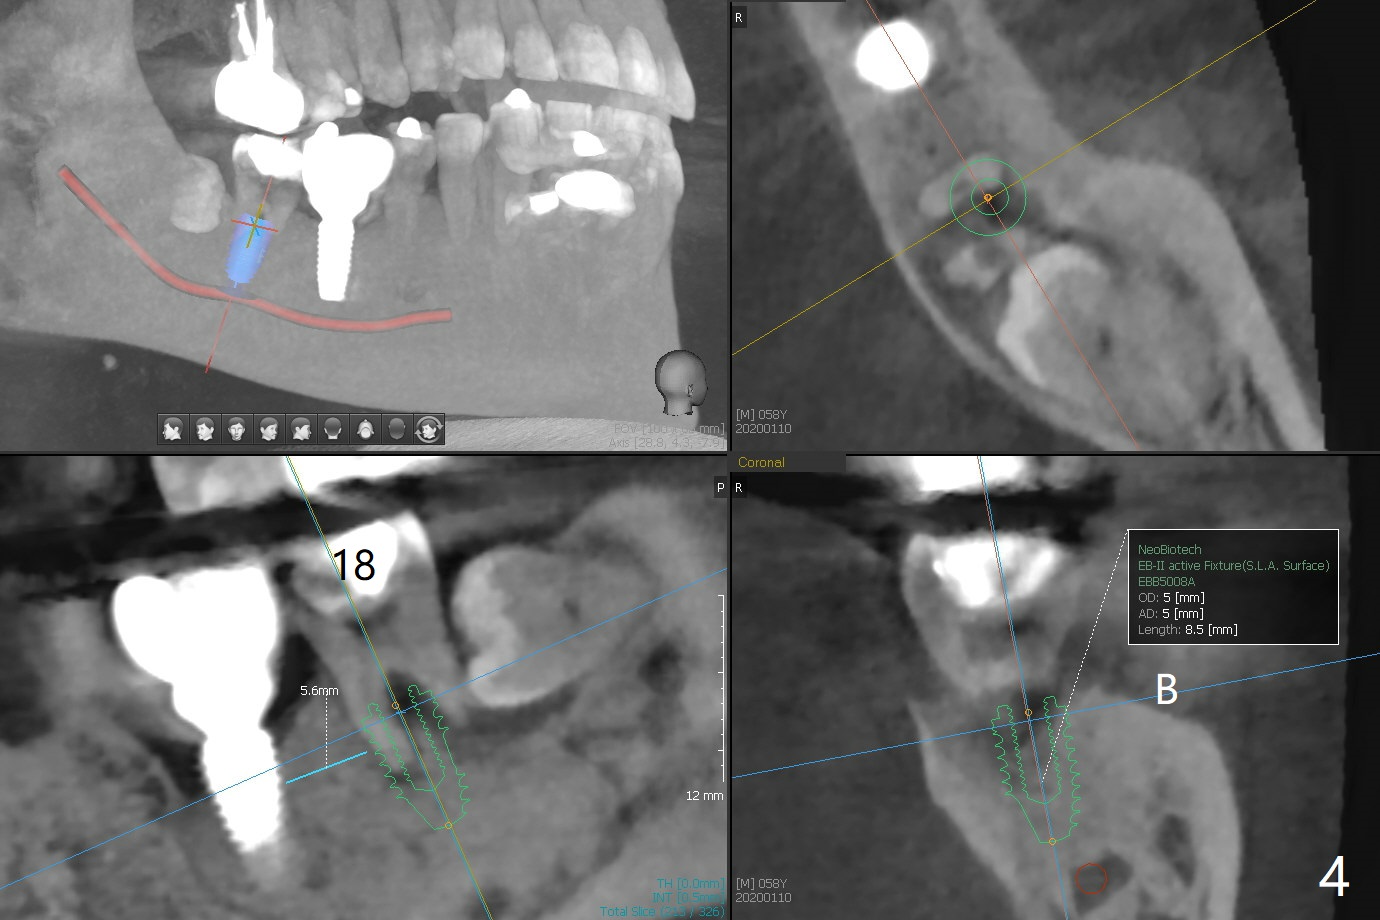

A 58-year-old man appears to have furca lesion or fracture the roots of the tooth #18 three years 5 months post cementation of #19 (Fig.1). In fact the abutment screw gets loose twice even with a buried screw driver. The implant at #18 will be a large tissue-level one (Fig.2). Use a thumb driver to place the implant initially through the metal sleeve for orientation. Although bone resorption mesial to #19 implant looks more severe in panoramic X-ray (Fig.3 *) and the sagittal view of CT (Fig.5) than PA (Fig.1), there is bone (less density) buccal (B) and lingual (Fig.5 *). Bone graft will be conducted at #19 if clinical exam confirms deep pocket the same time of #18 surgery. Distal radiolucency of #18 (Fig.3 *) makes it necessary to extract #17 simultaneously as well. Prepare Titanium brush.